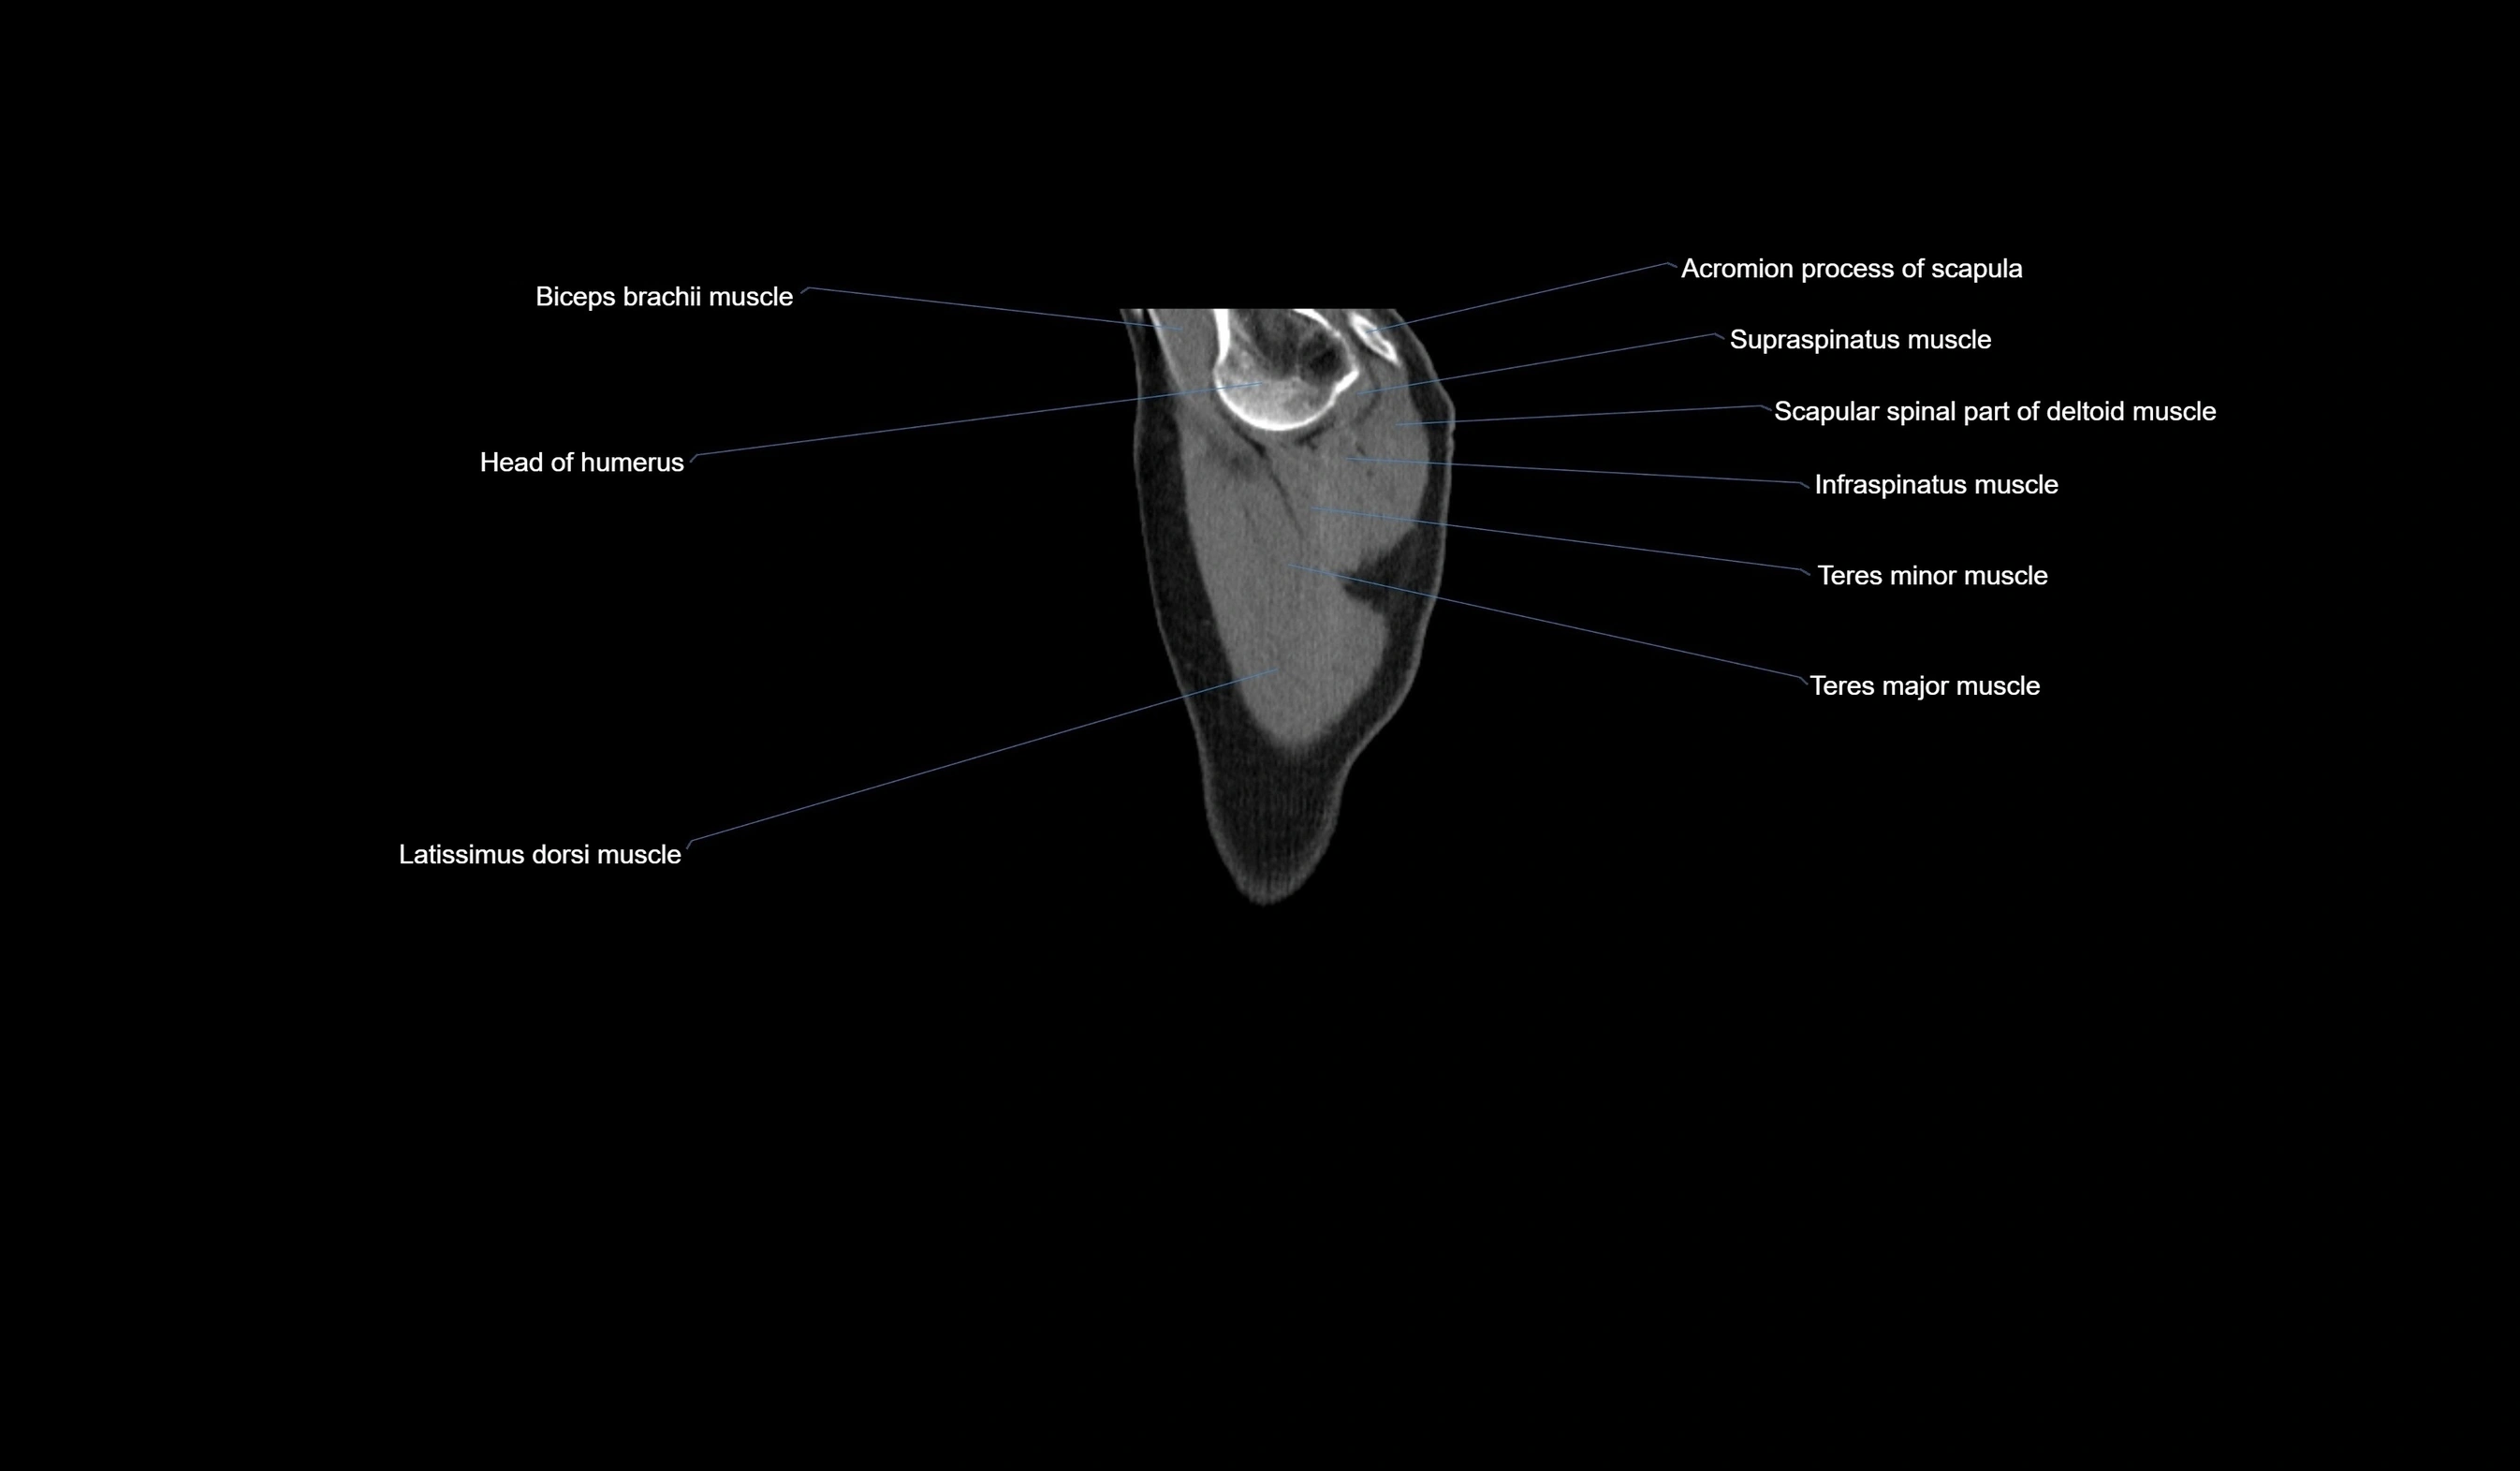

CT images